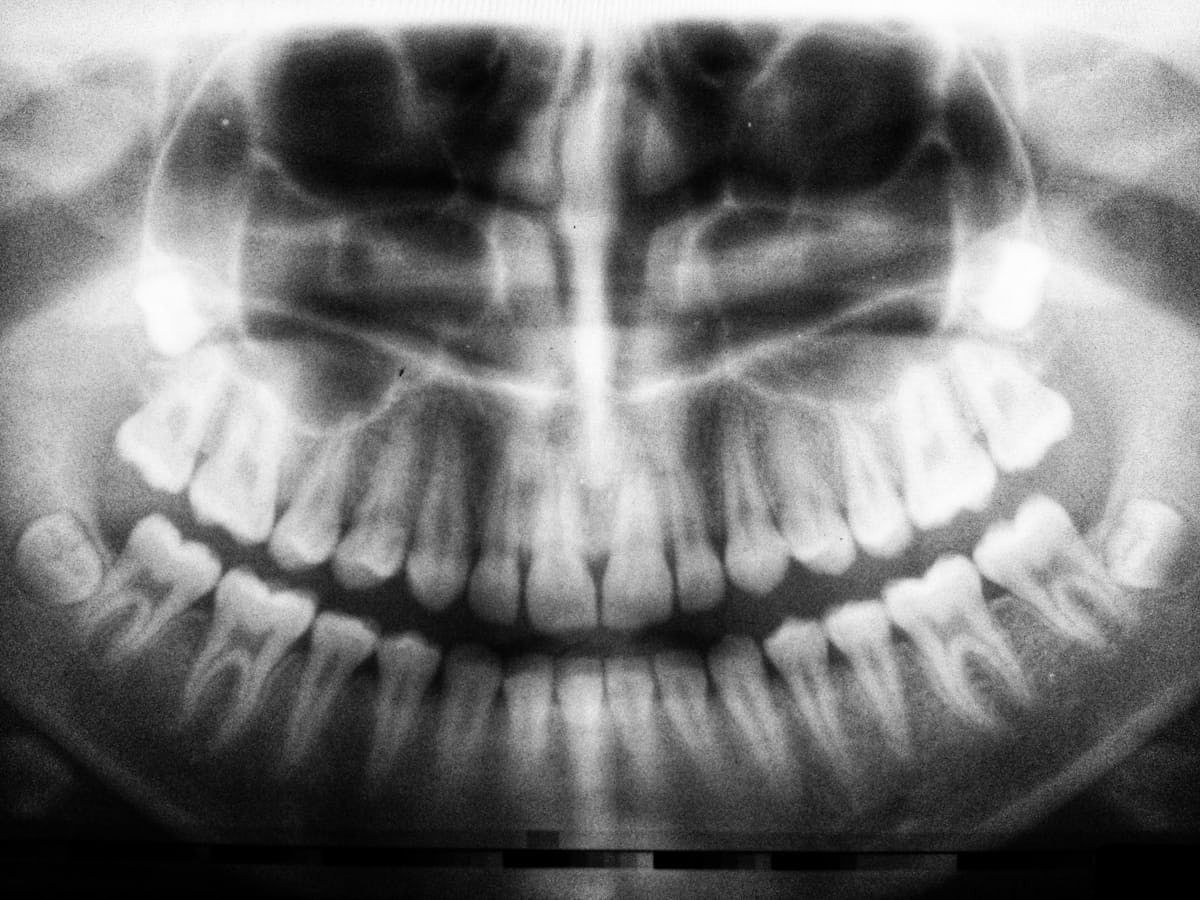

Prosthodontics is the superhero of dental care, crafting smiles with precision and flair. From restoring damaged teeth to creating stunning replacements, this field plays an essential role in dental health. Gone are the days when missing teeth meant missing out on life; we turn frowns upside down!

Prosthodontics offers solutions like crowns, bridges, and dentures to restore your smile and functionality.